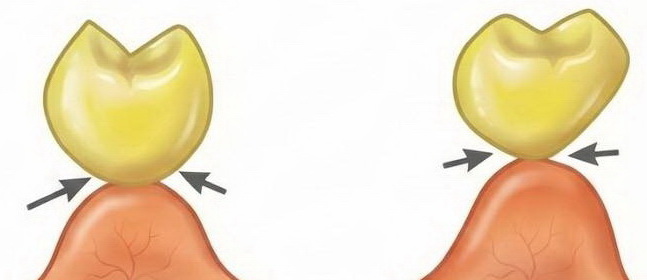

Răng giả nhịp cầu dạng ôm sống hàm (Ridge Lap Pontic)

- Tiếp xúc: Mặt đáy răng giả phủ lên sống hàm ở phía ngoài (má/môi) nhưng được cắt bỏ ở phía trong (lưỡi).

- Đặc điểm: Đảm bảo thẩm mỹ tốt ở mặt ngoài nhìn thấy, đồng thời cố gắng cải thiện khả năng vệ sinh ở phía trong.

- Thực tế trong lâm sàng: Đây là loại nhịp cầu mình ưu tiên dùng cho khoảng 80% các ca lâm sàng, đặc biệt là vùng răng tiền cối và răng trước. Nó đáp ứng được cả hai tiêu chí: vừa giúp bệnh nhân tự tin, vừa giúp họ dễ dàng dùng chỉ nha khoa hoặc bàn chải kẽ răng để vệ sinh mặt đáy nhịp cầu. Một lựa chọn cực kỳ an toàn cho độ bền lâu dài của phục hình.

Răng giả nhịp cầu dạng ôm sống hàm cải biên (Modified Ridge Lap Pontic)

- Tiếp xúc: Là dạng cải tiến của kiểu ôm sống hàm, trong đó răng giả chỉ tiếp xúc sống hàm ở mặt ngoài và ngay đỉnh sống hàm. Mặt trong được thiết kế lồi và không chạm niêm mạc.

- Đặc điểm: Diện tiếp xúc mô giảm đáng kể so với dạng yên ngựa hoặc ôm sống hàm cổ điển.

- Thực tế trong lâm sàng: Tính thẩm mỹ mặt ngoài tốt nhưng nhưng vẫn khó vệ sinh mặt trong, bệnh nhân thường khó chịu khi bị đọng thức ăn vùng mặt trong.